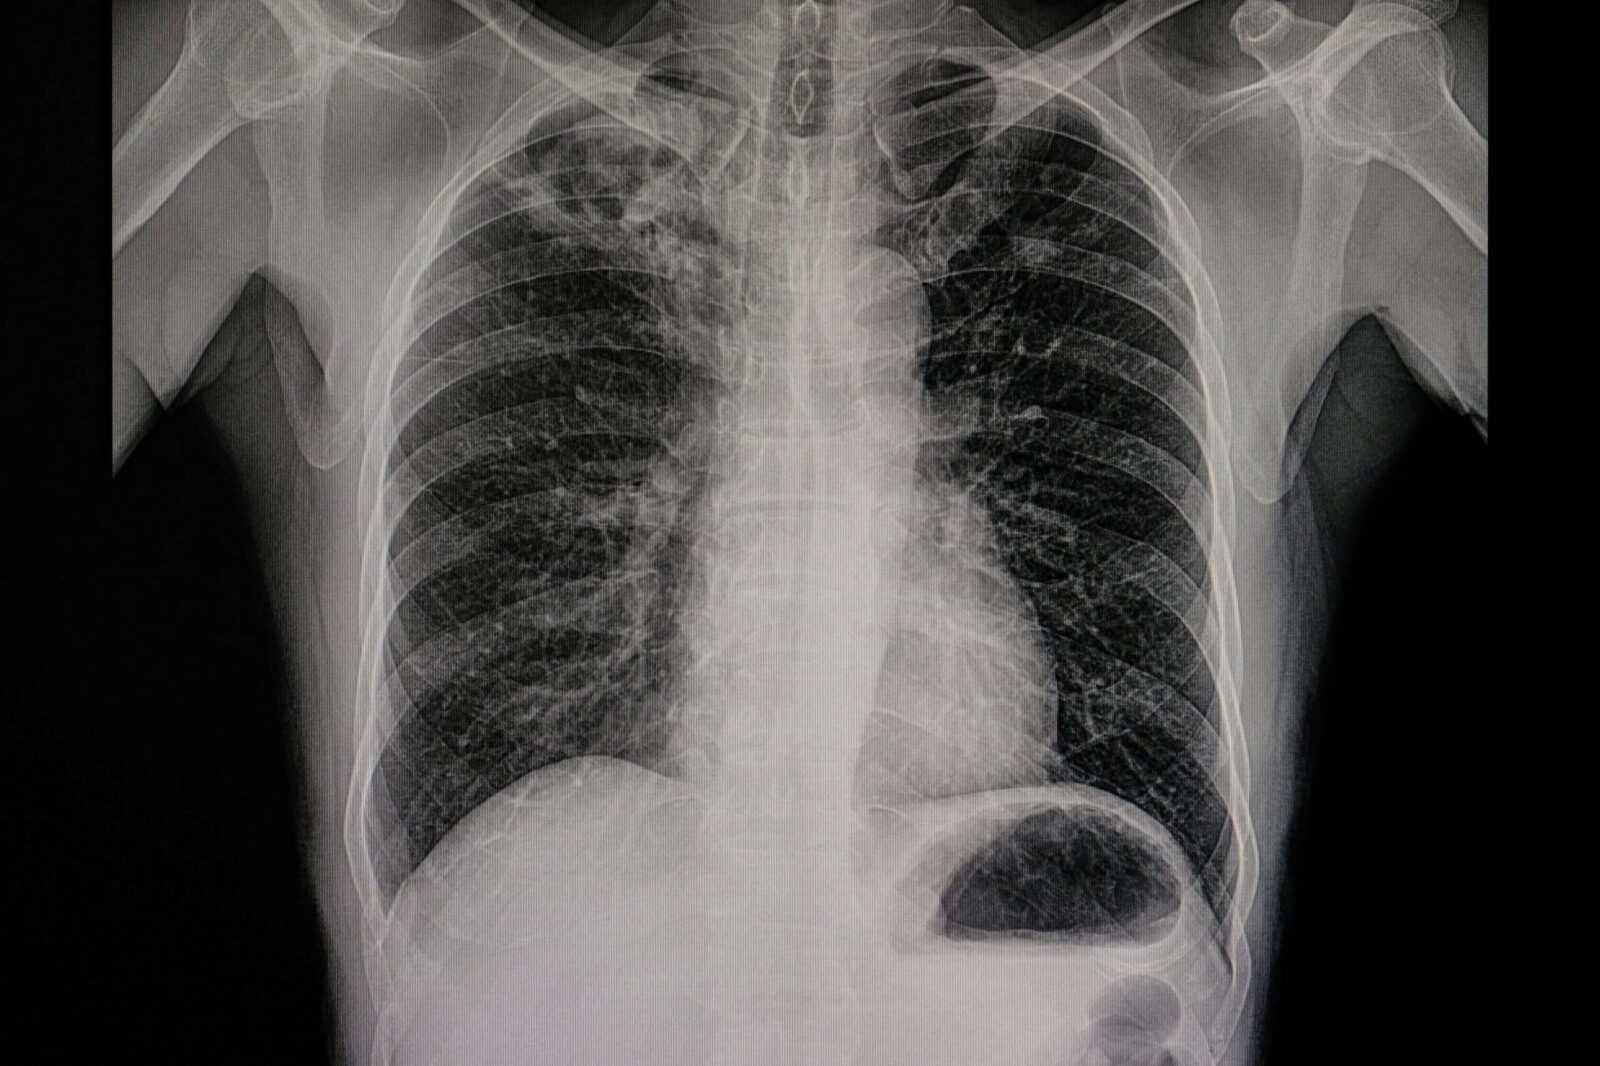

The doctor might request a chest X-ray or a CT scan based on a patient’s symptoms. Chest X-rays will allow your doctor to have a good view of the interior chest cavity, and if there is a questionable spot or shadow on a chest X-ray, the doctor may request a CT scan.

A CT scan will be very beneficial in this case as it can be used to capture images from different angles and depths and show deeper details of the body. This way, it will be easy to assess the nodule and diagnose based on its size and appearance.

Furthermore, a PET scan may also be required to determine if the lung nodule is malignant. Since every living cell in the body uses glucose to function normally. Cells that are malignant, i.e., growing faster than normal, will require more glucose than the others.

So, with a PET scan, a small amount of radioactive glucose is injected into a vein. After that, the scanner revolves around the body, identifying areas with the most significant glucose uptake.

Consequently, this may help diagnose a very big pulmonary nodule that takes up much glucose as malignant.